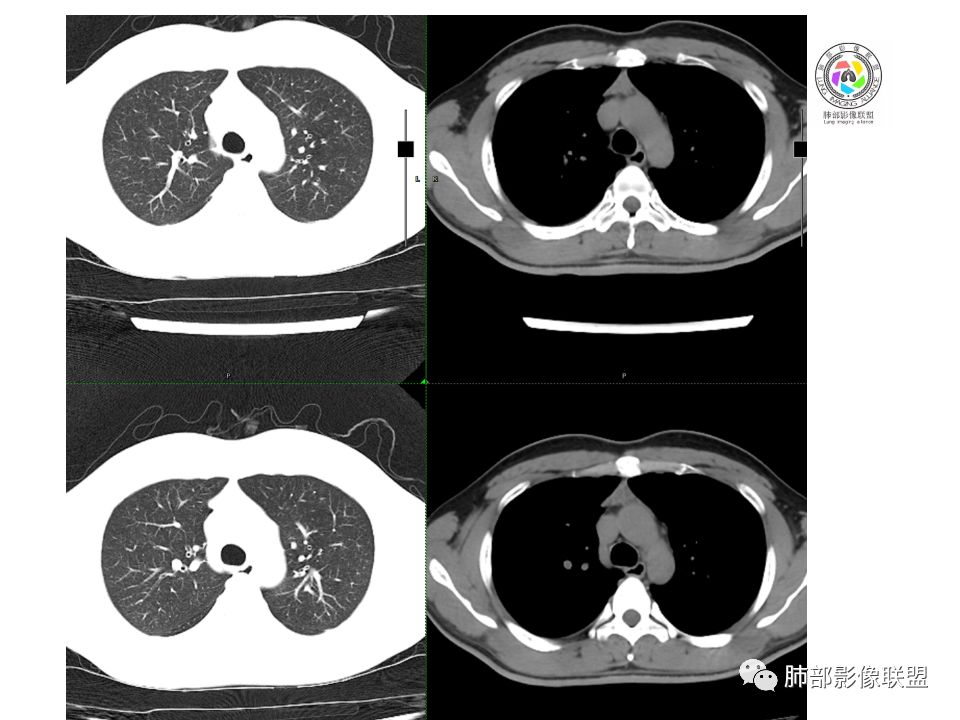

晨读:前纵隔占位,密度不均,沿着右侧纵膈延伸到肺门水平,周围支气管推移,大血管向内推移。临床有重症肌无力,考虑胸腺瘤可能,鉴别淋巴瘤。

患者青年人,前纵隔占位,无增强,猜一个淋巴瘤,不知道右下肺膨胀不全原因是什么

右前纵膈肿块,偏一侧生长,形态欠规则,密度不均匀,其内可见小点状钙化,双肺多发小叶中心结节及钙化灶,右侧胸膜增厚(有陈旧性结核可能),青年男性(27岁),没有增强,考虑,1,前纵隔生殖细胞瘤2,精源细胞瘤

右前上纵隔占位,瘤肺交界面清楚,提示纵隔来源,其内有点状钙化,右侧胸腔积液,有临床症状,年龄轻,考虑生殖来源可能,胸腺瘤待排,请结合临床相关检查或CT增强进一步检查。

前纵隔占位,伴点状钙化;上腔静脉后移位。伴右胸膜局限性增厚,临床有重症肌无力,病人年轻,考虑胸腺瘤可能,鉴别生殖源性肿瘤。

临床症状眼睑下垂,右纵膈占位,偏向一侧,有分叶,跟上腔静脉边界不清,淋巴结肿大,考虑胸腺瘤或胸腺癌

右前纵隔占位,有分隔`低密度、点状钙化,边缘光滑,侵袭心包不明确,伴右胸少量积水,考虑恶性,生殖源性可能大,有视物不清,是否脑转移待查。建议HCG丶AFP检查。鉴别1:胸腺瘤、癌,30一40岁以下,少见,但有眼脸下垂,肌无力,待排除。2:淋巴瘤:侵袭性不强,有点状钙化,不支持。3:畸胎瘤:有低密度丶钙化,建议增强进一步明确。4:神经源性:一般后纵隔常见,不支持。5:LCD:症状少见,可以有树枝状钙化,浆细胞型可以有低密度,增强进一步明确

前纵隔偏侧肿块,病灶内见点状钙化,症状肌无力,考虑恶性,胸腺瘤或神经内分泌癌

没有增强,好像两个病灶,上方三角形的像是胸腺增生。下方肿块,没有增强显得更难了,微钙化,轻度分叶,像有坏死低密度影,右侧少量胸水,胸膜受侵.,有视物模糊眼睑下垂。考虑胸腺瘤B1型及以上、B2型可能或生殖细胞瘤

患者年轻,有肌无力症状,除肿块外,前纵隔密度增高,与心包界限不清,考虑恶性。

前纵隔右区占位性病变,上区与胸腺延续,下区呈分叶状,尽管年龄<30还是首先考虑胸腺瘤,侵袭性可能性大(眼睑下垂不知是否有关)。鉴别主要是生殖细胞类肿瘤,主要是精原细胞瘤。另左肺上叶结核球,右侧胸腔积液,需除外结核性胸膜炎和转移

前纵隔占位性病变,偏向一侧生长,密度不均,可见点状钙化,考虑胸腺瘤,鉴别精原细胞瘤

临床肌无力加前纵膈占位,首先考虑胸腺瘤

晨读:前上纵隔病变,结合病史,考虑胸腺瘤可能,不除外淋巴瘤。

结合临床,尽管年龄轻,也得首选胸腺瘤

右前纵隔肿块,边界清楚,密度欠均匀,内似有分隔和低密度区,似有多结节融合,几乎从上到下,年龄较轻,不是胸腺瘤好发年龄,但却有视物模糊,眼睑下垂症状,考虑淋巴瘤?鉴别胸腺瘤?结核?

右前纵隔肿块,结合病史,先考虑胸腺瘤可能,待排生殖类肿瘤

右前纵隔肿块,结合病史,虽然年龄小于30岁,但症状太符合了,先考虑胸腺瘤可能。

考虑胸腺瘤,左肺上叶良性结节钙化

右前上纵膈肿块,内有点状钙化和少许小片状坏死,局部边界似欠清,右侧胸膜腔少量积液,年轻男性,小于30岁,有重症肌无力,虽然年龄偏轻,仍先考虑胸腺瘤,代排生殖源性肿瘤

晨读前纵隔肿块,偏右侧,密度不均,见点状钙化灶及分隔状低密度影。胸腺瘤>生殖细胞瘤>淋巴瘤

前纵膈占位,上腔静脉受推移,有分叶密度较均匀,结合临床考虑胸腺瘤,待排生殖细泡瘤.淋巴瘤

前中纵隔(胸腺癌区)不规则肿块,密度不均,有坏死区、点状钙化,边缘不会整肿块偏向右侧,向心包流注感,右胸腔少量积水。患者27岁,重症肌无力表现。